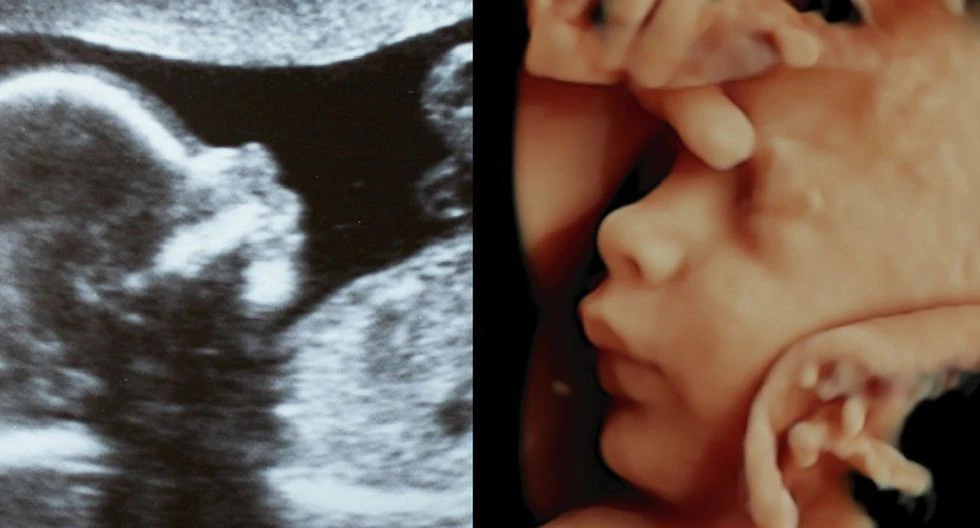

Madre, he ahí a tu hijo: así es una Ecografía 7D , con la que ya se pueden ver detalles del cerebro y el corazón

Esta tecnología cumple seis décadas con nosotros. Ahora, los nuevos equipos permiten ven a los bebes con una nitidez extraordinaria, como si hubiera una cámara dentro del vientre materno. Incluso, hasta usan Inteligencia Artificial.

Ecografía 7D ¿Cómo se realiza este nuevo método de diagnóstico que incluye la Inteligencia Artificial?

El estudio del bebe ahora es más preciso e intuitivo gracias a esta nueva tecnología ecográfica, que permite detectar si al bebe le falta oxígeno y nutrientes.